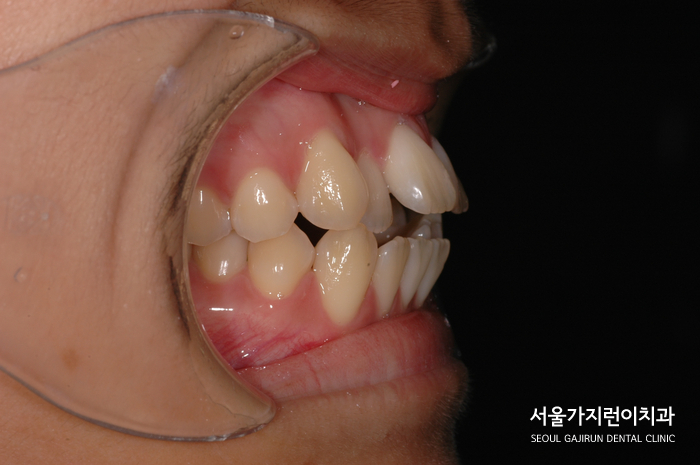

환자분의 경우 앞니가 돌출되어있었고 아래 치아는 배열이 무너진 상태였습니다.

특히 앞니가 닿지 않는 상태 '개방교합'에 불규칙한 치열, 덧니도 나와있어 음식 섭취나 발음에도 불편함이 있었는데요.

치아 사이에 공간이 부족해서 치열이 더 쏠려 악화될 우려도 있었습니다.

여기에 돌출입 증상까지 더해 치아배열 조정이 시급했는데요. 위아래 치열의 맞물림을 유도하는 방식으로 치료를 시작했습니다.